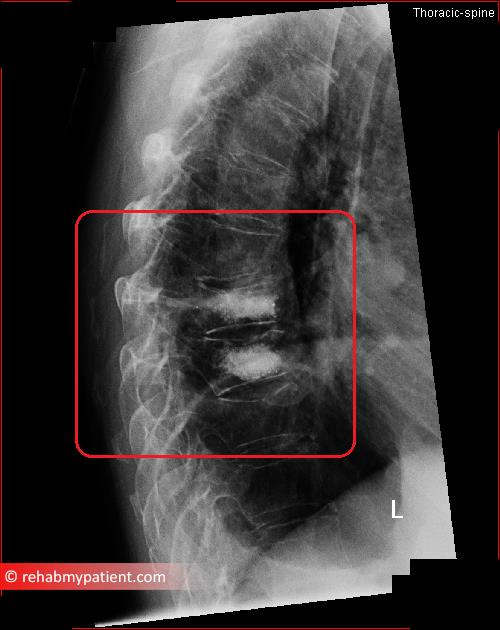

from www.rehabmypatient.com

Kyphoplasty Rehab My Patient

Kyphoplasty Rehab My Patient How Many Times Can You Have Kyphoplasty In some cases, you may feel. If you have a compression fracture of the spine, kyphoplasty is a procedure that might help relieve pain. Kyphoplasty is a minimally invasive procedure where bone cement is injected to stabilize vertebral compression fractures for immediate pain relief. Kyphoplasty can restore a damaged vertebra’s height and may also relieve pain. A couple of hours. How Many Times Can You Have Kyphoplasty.